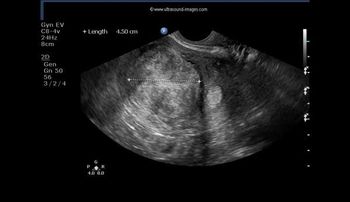

Excessive traction blamed for brachial plexus injury; bowel injury after laparoscopy; prolonged second stage blamed for CP; failure to perform timely cesarean blamed for child’s developmental delay; uterus perforated during hysteroscopy; severe IUGR not detected in high-risk pregnancy